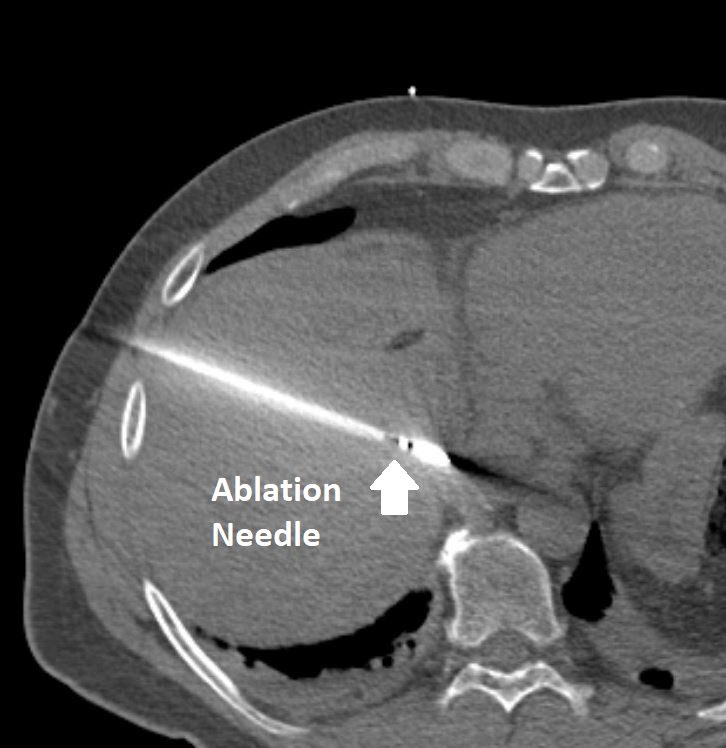

Image-guided ablation by interventional radiology (#IRad), where a thin needle placed through the skin burns the #cancer to death, has similar outcomes to surgery for select patients with liver cancer. This outpatient procedure has fewer complications than #surgery.

Interventional radiology (#IRad) is an important partner in caring for patients with liver disease, from relieving portal hypertension to opening obstructed bile ducts to killing #cancer. This small #cancer was burned to death via a small needle placed under CT guidance.